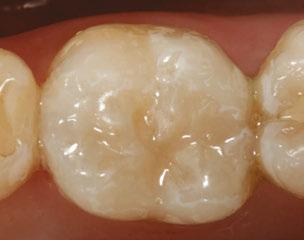

The 5-year-old patient featured in this case study did not benefit from early oral care and had multiple carious lesions. Considering the young age, high caries risk, and the uncertainty of compliance with follow-up appointments, I wanted to restore and seal all teeth in one visit. One quadrant is shown in this case study. The carious lesion on tooth J (65) was cavitated and prepared, restored, and sealed. Tooth I (64) was non-carious and would only be sealed (Figure 1).

I chose Activa™ Kids Bioactive-Restorative and Activa Presto (Pulpdent) as restorative materials for this case because I have seen excellent clinical results over time with these bioactive materials. Continuous release and recharge of calcium, fluoride, and phosphate from these restoratives are beneficial in the fight against decay long into the future.

Choosing restoratives based on ease of use and the ability to work quickly was important in this case. All restorations were completed under general anesthesia in one appointment. There were wear facets on the occlusal surfaces of the molars, so it was important to use a material that would have some flexibility and resistance to fracture. The innovative composition of Activa Kids includes an elastomeric monomer or “rubberized” component that absorbs forces and was an ideal filling material. Activa Presto shares similar properties, and it was convenient to use as an occlusal surface sealant for this patient.

Tooth J (65) was prepared with a coarse tapered high-speed diamond bur allowing for some minor mechanical retention by incorporating minimal undercut in preparation. The occlusal

surface of tooth I (64) was also lightly abraded with a diamond bur (Figure 2). The preparations were selectively etched with phosphoric acid, rinsed, and lightly dried (Figure 3). Bonding agent was applied to the entire occlusal surfaces of both teeth, air thinned, and light-cured (Figure 4).

Tooth J (65) was bulk-filled with Activa Kids. For this fast injection technique, I place the dispensing tip at the floor of the preparation and extrude the material without removing the tip until the preparation is completely filled (Figure 5). I like to do some minor manipulation of the filling material with hand instruments to create anatomy, as well as to ensure the material is flush with the surface of the preparation, and no air is trapped inside. Activa Kids is dual-cure, ideal for bulk filling, and can be cured with all lights. A thin topcoat of Activa Presto was placed as a sealant on the entire occlusal surface of teeth I and J (64 and 65) (Figure 6). Figure 7 shows the final clinical situation.

Figure 1 (left): Caries lesion on tooth J (65). Figure 2 (center): Preparation of tooth J (65) and abraded occlusal surface of tooth I (64). Figure 3 (right): Selective etch of enamel Figure 4 (left): Bonding agent is applied to both teeth I and J (64 and 65). Figure 5 (right): The preparation is filled with ACTIVA Kids Figure 6 (left): A thin topcoat of ACTIVA Presto is applied to the occlusal surfaces of teeth I and J (64, 65). Figure 7 (right): Final result